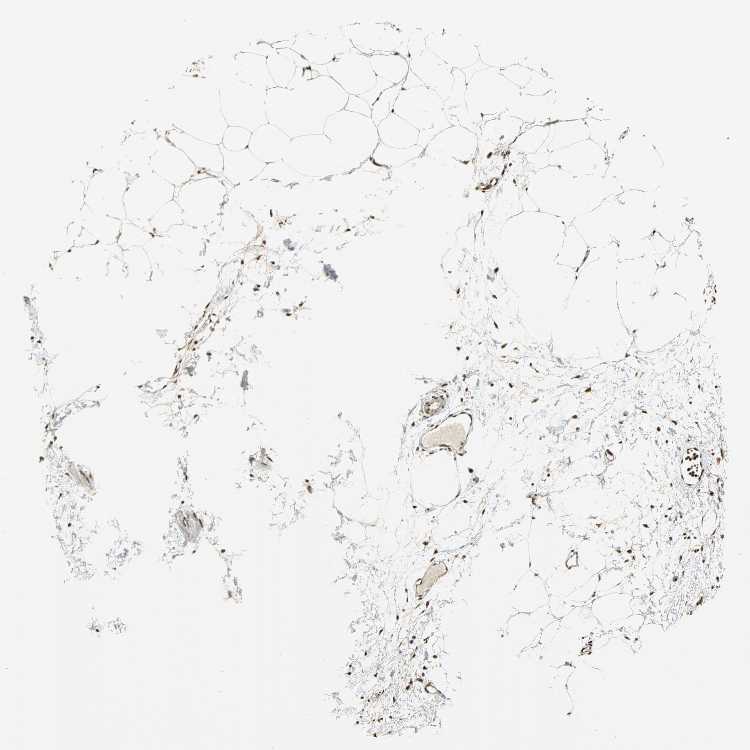

ADIPOSE TISSUE - Antibody stainingi

Antibody staining in the annotated cell types in the current human tissue is reported as not detected, low, medium, or high, based on conventional immunohistochemistry profiling in selected tissues. This score is based on the combination of the staining intensity and fraction of stained cells.

Each image is clickable and will lead to virtual microscopy that enables deeper exploration of all samples and also displays staining intensity scores, fraction scores and subcellular localization as well as patient and tissue information for each sample.

Antibody HPA006195Antibody HPA006474

Adipocytes MediumHigh